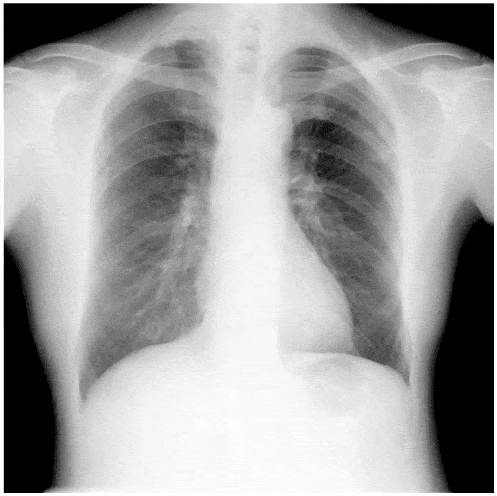

デジタルX線動画撮影システムとは

デジタルX線動画撮影システム(Dynamic Digital Radiography)は従来の単純X線撮影と同様に、一般X線撮影装置を用いて簡便に撮影できる新たな検査法であり、回診用X線撮影装置「AeroDR TX m01」によりベッドサイドでのX線動画撮影が可能となり、更なる広がりを見せています。

| タイトル | DDR臨床セミナー ~胸部単純画像の基本からX線動態画像の臨床での活用まで~ |

本当は教わりたかった!?ポータブル胸部X線写真の読み方 2025 ~動態検査での知見も交えて~ 松本 純一先生 聖マリアンナ医科大学 救急医学 講師 |